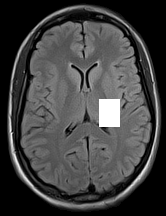

3.1.3 Example 2: data driven reconstruction methods in lung CT screening

There is sufficient evidence that screening for certain tumours using CT images may improve prognosis of cancer survivability (citep \@BBN(Boiselle, 2013)). As mentioned above, in order to gain better image quality with less X-ray dose, many enhanced regularization techniques with integrated machine learning steps have been suggested for CT reconstruction, and in a full reference setting they are commonly evaluated by applying PSNR and SSIM, see e.g. (citep \@BBN(Adler and Öktem, 2018; Hendriksen, Pelt, and Batenburg, 2020; Unal, Ertas, and Yildirim, 2021)). As CT images are generally taken to perform a clinical task, they are not the final step of a medical process but often the initial one. Therefore the definition of what makes a good image heavily depends on the task in hand, and for prognosis related cancer the identification of tumours is of upmost importance.

In on-going research on photon counting detector types and screening procedures for lung cancer (EPSCR grant: EP/W004445/1) an experiment was conducted testing enhanced reconstruction algorithms. Simulations using less than 10% of a clinical X-ray dose were performed to investigate if data-driven methods could sufficiently enhance the images to clearly see the tumours in the lungs while providing very low amount of dosage to the patients. The corresponding data was a CT-dose simulation, using images from the open LIDC-IDRI dataset (citep \@BBN(Armato et al., 2011)) as references, as well as simulated and reconstructed images with in-house software. Figure 3 shows the results of the experiment. We show the reference image used as basis for the simulation, together with five different reconstruction algorithms. The first is an iterative solver, a gradient descend algorithm with TV minimization (citep \@BBN(Sidky et al., 2012)) and (c)-(f) correspond to machine learning methods: FBPConvnet is a denoising algorithm that cleans the bad image (citep \@BBN(Jin et al., 2017)), LPD is an iterative unrolled method that combines traditional solvers with machine learning (citep \@BBN(Adler and Öktem, 2018)), Noise2Inverse is a self-supervised learning method (i.e. does not require ground truth data) (citep \@BBN(Hendriksen et al., 2020)) and ItNet is another iterative unrolled method, the best performing winner of the AAPM DL-Sparse-View CT challenge (citep \@BBN(Genzel, Macdonald, and März, 2021)). ItNet is also judged here as the best result according to PSNR, SSIM and LPIPS.

Refer to caption

(a) Reference

(b) (27.6, 0.70, 0.37)

(c) (31.9, 0.73, 0.29)

(d) (32.5, 0.84, 0.19)

(e) (32.5,0.77, 0.20)

(f) (33.0, 0.89, 0.12)

Figure 3: Reference image (a) and outputs of different reconstruction methods (b)-(f) applied to dose simulated data. PSNR/SSIM/LPIPS are unable to identify the best reconstruction (c), where also the tumour is visualized well.

FR-IQA mismatches

This experiment was performed to evaluate the quality of different kinds of CT reconstruction, and especially the lung tumour detection capabilities thereof. The best result according to the chosen IQA measures is given by ItNet in Figure 3(f), which performs visually poorly. Not only the tumour (zoomed in white circle) is significantly less visible in the reconstruction, but ItNet also produces structures in the lung that are different than the ones in the reference image; it blurs and lengthens much of the soft tissue present in the lungs and it also created structure from noise in some places. Moreover, the image is overly smooth. Comparing the other reconstruction algorithms, it seems that FBPConvnet Figure 3(c) is the one performing best at preserving the shape of the lung nodule, even when the resulting image contains enhanced pixel-level noise.

We can see here that the qualitative findings strongly contradict the numbers provided by the selected measures. The reconstruction of ItNet, Figure 3(f), is outperforming the other reconstructions in regards of the measures, and the qualitative winner FBPConvnet, Figure 3(c), is judged as second worst by the same measures. This experiment suggests that the discussed measures are not a good choice for that kind of CT reconstruction applications and are yielding misleading results.

While pixel-independent random noise may be a worse effect in a natural image than a slightly oversmooth reconstruction, this is not true in CT images, where small structures may disappear if smoothing is promoted against edge preservation. In iterative reconstruction algorithms such choices are explicitly made by choosing the prior appropriately, in data-driven models the researcher has limited control on the type of implicit priors the algorithm learns from the data, i.e. model builders do not know what the algorithms chooses to learn from the ground truth. In these cases appropriate evaluation would therefore be even more important to ensure quality. If this is followed by a blind evaluation using non-appropriate metrics, the promotion of less desirable images can happen, chosen by an implicit assumption on the metric rather than the actual goal of the task.